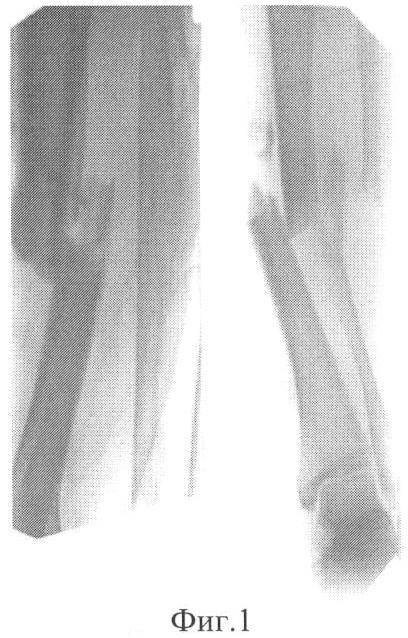

Фиг.1 – рентгенограмма голени больной до лечения;

Больная Е., 25 лет, история болезни 23270, поступила с диагнозом: открытый оскольчатый перелом обеих костей правой голени в средней трети с полным смещением отломков; дефект мягких тканей в средней трети голени (Фиг.1).